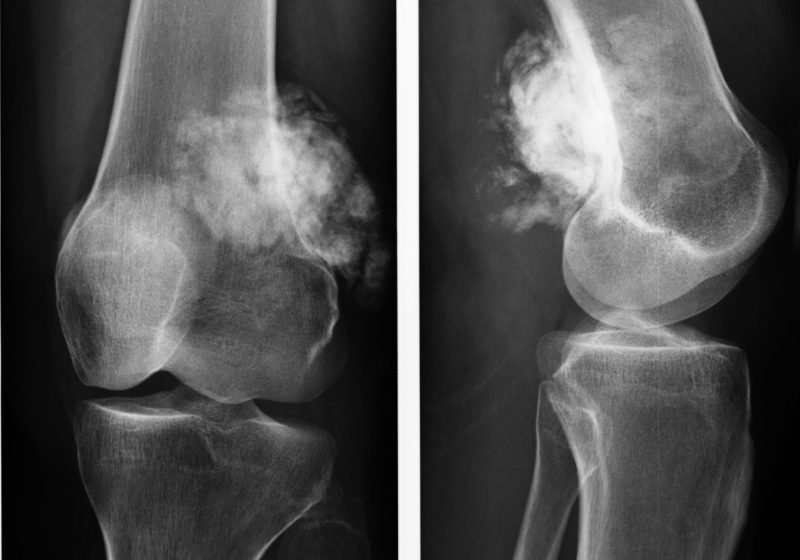

Тщательный сбор анамнеза – личного, семейного, профессионального, а также жалоб больного помогает специалисту выставить предположительный диагноз, подтвердить который или опровергнуть могут следующие диагностические исследования:

- рентгенография – наиболее широко распространенный и общедоступный метод, помогающий выявить отклонения в плотности костных структур;